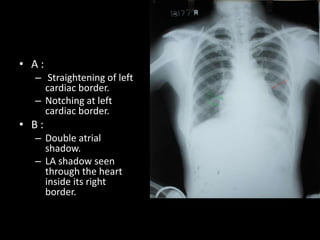

• A:

– Straightening of left

cardiac border.

– Notching at left

• B:

– Double atrial

shadow.

– LA shadow seen

through the heart

inside its right

border.

• A: – Straightening of left cardiac border. – Notching at left cardiac border. • B: – Double atrial shadow. – LA shadow seen through the heart inside its right border.